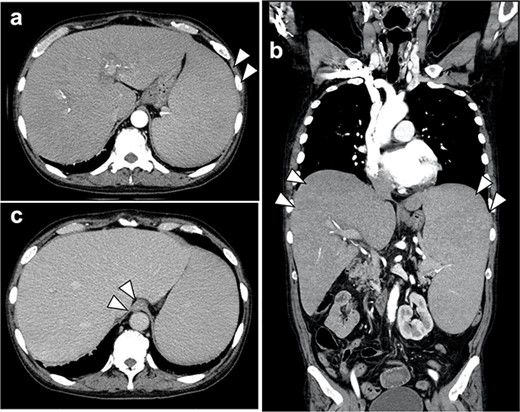

Abdominal computed tomography (CT) scans showed esophagogastric varices, but no gastric cancer lesion could be identified (Fig. 2).

(a, b) Contrast-enhanced CT scan of the abdomen showed marked hepatosplenomegaly due to myelofibrosis; there was no extravasation of contrast medium into the gastroesophagus; no gastric cancer lesion could be identified; (c) the accumulation of contrast media in the lower esophageal wall of the esophagus was observed in the late contrast phase, which was varicose veins.